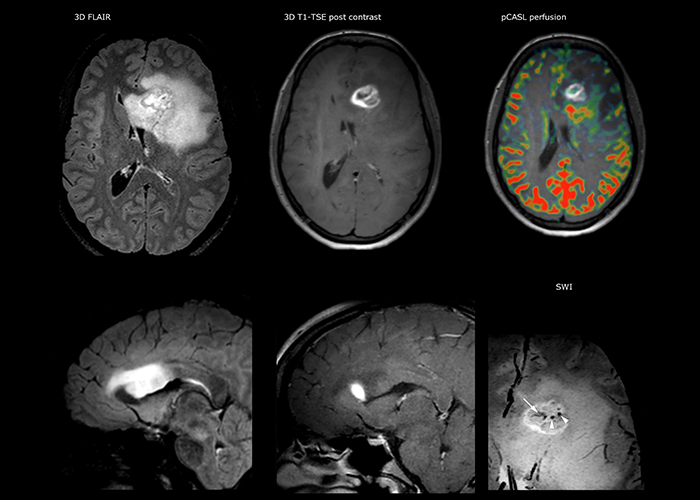

Dr. Savatovsky uses five or six different ExamCards for imaging a mass or a known tumor in the brain. “If there is a mass in the brain we try to characterize it to inform the neurologist for determining next steps or to help neurosurgeon prepare for a surgery or biopsy. For follow-up after treatment we have different protocols for different treatments and we adapt for intra- or extra-axial tumors.” “That is the most comprehensive exam we would do. Ingenia has the good spatial resolution and high SNR to provide all this information, and the flexibility to use shorter sequences, so we can do a very comprehensive examination in a limited time.”

“The biggest challenges are properly characterizing the lesion and giving the surgeon all the information needed, such as the location of vessels and functional areas. Sometimes a very comprehensive exam is necessary, such as when a mass has been discovered at another hospital after which the patient is referred to us. We then do both lesion characterization and preoperative imaging in one exam, so both morphologic and functional assessment. For morphologic assessment we will use pre- and post-contrast T1-weighted imaging, FLAIR to assess infiltration, and diffusion. For functional characterization we will perform perfusion, spectroscopy, and susceptibility weighted imaging to look for micro vessels or micro hemorrhage inside the lesion[4]. For preoperative imaging we perform specific morphologic imaging that is compatible with the navigation system; depending on the location of the tumor, we would do fMRI or DTI.”